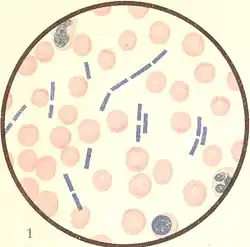

Erreger

Der Milzbranderreger, Bacillus anthracis, gehört zur Gattung Bacillus (sporenbildende, aerobe Stäbchenbakterien) innerhalb der Familie Bacillaceae. Er ist ein etwa fünf bis sechs µm (1 µm = 0,001 mm) langes, grampositives, unbewegliches, sporenbildendes Stäbchen, das in Körperflüssigkeiten kurze, in der Kultur längere kettenförmige Verbände bildet („Serpentinen“- oder „Medusakopf“-Form). Im Tierkörper ist die Bakterienzelle von einer deutlichen Kapsel (bestehend aus D-Glutamat) umhüllt, während in der Kultur in der Regel keine Kapselbildung erkennbar ist. Außerhalb des Tierkörpers, in Anwesenheit von Sauerstoff und bei Temperaturen von 12 bis 43 °C, bilden sich Sporen (Dauerformen), deren Größe etwa 0,5 bis 1,2 µm beträgt.

Zur Absicherung werden die Anthrax-Bazillen aus den Hautschäden oder bei Verdacht auf Lungenmilzbrand aus dem Auswurf gewonnen und mikrobiologisch untersucht. Gegebenenfalls wird auch eine Blutprobe untersucht. Für den Erregernachweis kommen drei Methoden in Frage. Zum einen wird der Erreger direkt mikroskopisch nachgewiesen. Zum anderen kann der Nachweis anhand einer Bakterienkultur erfolgen. Zum dritten ist ein molekularbiologischer Nachweis mit der PCR möglich. Dazu wurde in jüngster Zeit auch ein Schnelltest entwickelt.